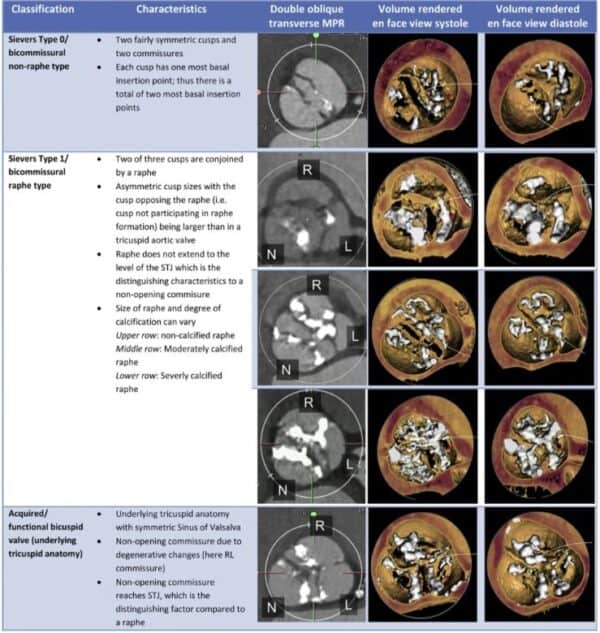

En segundo lugar, es muy importante cuantificar la severidad de la calcificación valvular. Tambien, se debe de determinar si la válvula aórtica es bivalva o trivalva (muy importante cuando existe dilatación aneurismática de la aorta ascendente).

calcificacion de aorta bivalva sievers